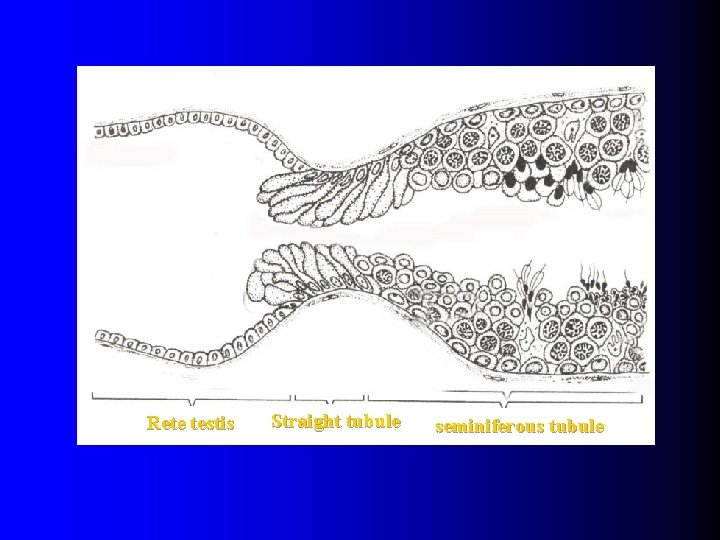

(三)straight tubule & rete testis l Straight tubule: near the mediastinum of the testis , where seminiferous tubule assume a short straight course. l Rete testis: the straight tubule empty into the rete testis, an anastomosing channel system within the mediastinum. l Sperm produced in seminiferous tubule pass by straight tubule & rete testis , leaving testis and arriving in epididymis.

Rete testis Straight tubule seminiferous tubule